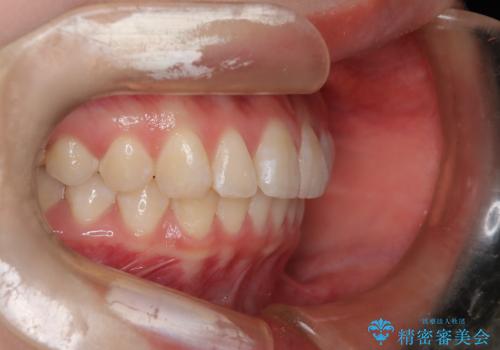

前歯のガタつきを治したい 翼状捻転マウスピース矯正

- 上顎前歯の突出、がたつき(翼状捻転)を主訴に来院されました。当院では総合歯科医療が可能であるため、矯正前処置として虫歯治療・歯周治療、親知らず抜歯を施行しました。その後、非抜歯かつ口元が出ないようなマウスピース治療を行いました。仕事柄、1日の装着時間が短くなってしまう時期もありましたが、患者様と相談しながら問題なく終了しています。